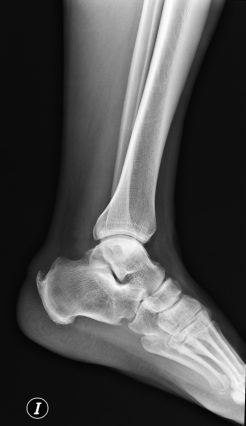

SINDROME DE HAGLUND.

El sindrome de Haglund describe un tipo especifico de tendinosis insercional que se asocia con una prominencia osea (deformidad de haglund) que se extiende desde el aspecto posterosuperior del calcáneo. Se produce la siguiente triada:

Existe dolor posterior y puede asociar además espolones calcáneos. Se da frecuentemente en mujeres que usan tacones.

- Deformidad de Haglund.

- Chauveaux-Liet angle mayor de 12º.